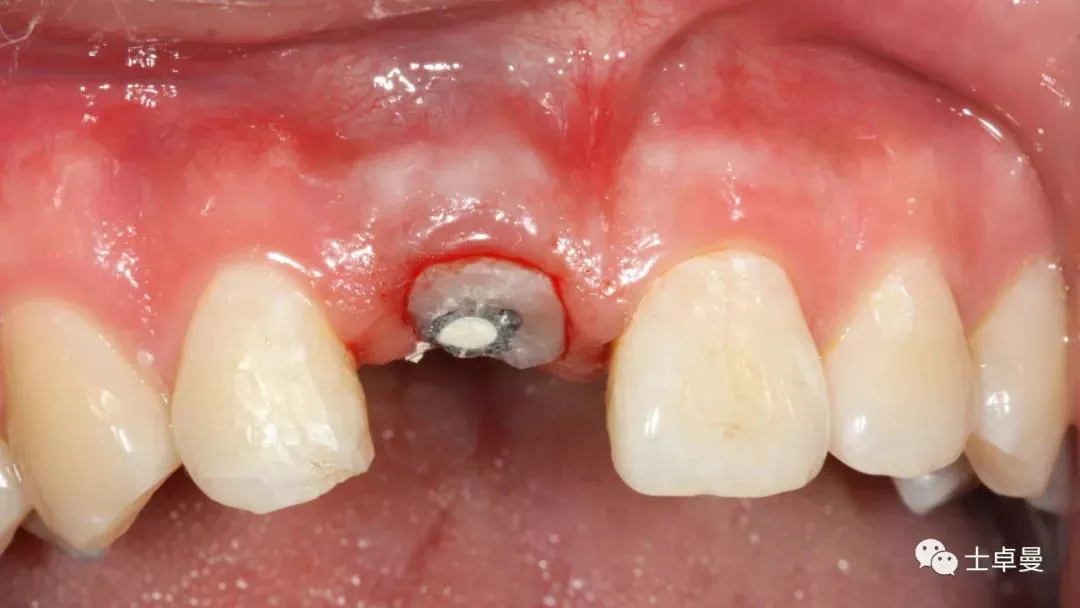

术后1个月,取下马里兰桥,可见骨弓轮廓可,软组织无炎症

术后4个月复查,软组织无炎症

术后4个月复查,种植体周未见明显暗影